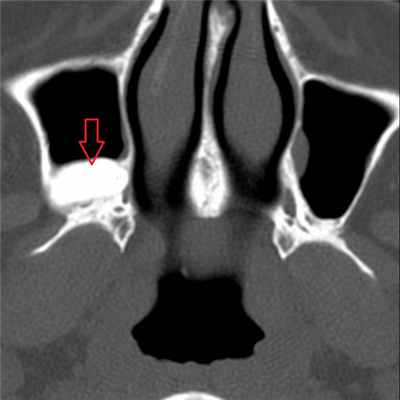

На рентгеновском снимке о наличии кисты можно говорить в случае, если в проекции пазухи имеется затемнение с краем, который может являться частью круга. Центр данного круга должен при этом находиться внутри пазухи, а не за ее пределами – в таких случаях речь идет, скорее, о наличии жидкости в пазухе (вязкого характера) или об ином экссудативном процессе. На рентгенограммах пазух кисты могут давать и картину тотального затемнения пазухи – в этом случае необходима дифференциальная диагностика с экссудативным гайморитом, муко- и пиоцеле, опухолью и т. д. На рентгенограмме определяются кисты верхнечелюстных пазух с обеих сторон. Обратите внимание на верхний край затемнения в пазухах – он ровный, имеет полукруглую форму, характерный для кист вид. В данном случае с целью уточнения размеров и локализации кист необходима компьютерная томография околоносовых пазух. Характерная для кисты верхнечелюстной пазухи картина при компьютерной томографии: обратите внимание на объемное образование в правой гайморовой пазухе, которое имеет ровные, закругленные края (отмечены стрелкой красного цвета), однородную структуру и плотность, соответствующую жидкости (+5…+15 единиц по шкале Хаунсфилда). Видно также, что выводной проток пазухи сужен, слизистая ячеек этмоидальной пазухи с правой стороны утолщена, имеет место утолщение слизистой носа – все это признаки катарального этмоидита, ринита, возникшего вследствие нарушения мукоцилиарного клиренса. Не путайте кисту верхнечелюстной пазухи с пролабирующим в полость пазухи корнем зуба (отмечен стрелкой) – на рентгенограммах очень часто тень зуба дает картину, имитирующую кистозное образование в пазухе – зачастую только с помощью КТ пазух можно различить эти два состояния. На данных изображениях также представлена киста гайморовой пазухи справа – обратите внимание на аксиальный срез (слева). Только по одному аксиальному срезу сложно сделать вывод о том, что за образование находится в полости пазухи, однако при выполнении реформаций в сагиттальной плоскости можно убедиться, что это именно киста большого размера (по характерному для кисты ровному закругленному краю, отмеченному стрелкой). Также на изображении справа видно, что слизистая оболочка гайморовой пазухи справа утолщена, а в ячейках решетчатой кости с этой же стороны визуализируется содержимое в большом количестве, выводные протоки гайморовой и этмоидальной пазух не прослеживаются. В данном случае наличие большой кисты в гайморовой пазухе спровоцировало развитие воспалительной реакции слизистой и явилось причиной правостороннего этмоидита. На изображениях можно проследить следующую патологию – часть этмоидальной пазухи пролабирует в полость носа (пролабирующая ячейка заполнена содержимым жидкостного – исходя из ее плотности – характера; отмечена стрелкой). Утолщена также слизистая верхнечелюстных пазух, резко сужены их выводные протоки (отмечены цифрой 1 на левом скане). На изображениях в аксиальной плоскости (слева), сагиттальной (в центре) и корональной (справа) плоскостях видна киста правой гайморовой пазухи. На КТ она выглядит как образование с ровными краями, жидкостной плотности (обозначена на всех сканах красными стрелками). На крайнем правом скане также цифрой 1 обозначена правая половина этмоидальной пазухи, заполненная содержимым. Имеются также признаки катарального гайморита (на левом скане) – оцените слизистую оболочку левой гайморовой пазухи – она явно утолщена. Небольшая киста гайморовой пазухи на КТ справа. Отмечена стрелками. Располагается пристеночно у задних отделов медиальной стенки и нижней стенки пазухи. Не вызывает нарушений отхождения слизистого секрета из пазухи.